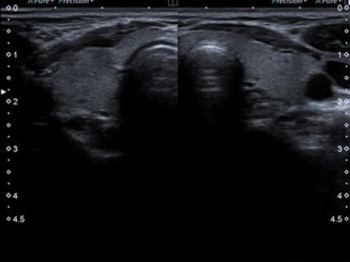

PAROTİS ULTRASONU

Parotis enfeksiyonlarından en bilineni genellikle çocukluk çağında görülen kabakulaktır. Kabakulak dışında viral ve bakteriyel enfeksiyonlar gelişebilir. Bu durumlarda renkli doppler ultrason tanı açısından önemlidir. Parotisin iyi ve kötü huylu kitleleri mevcuttur. Ultrason incelemesinde parotis kitlesinin şekli, anatomik özellikleri ve doppler inceleme özelliklerine bakılarak tanıya yardımcı olunabilir. Eğer kitle kötü huylu olma potansiyeli taşıyorsa ultrason eşliğinde ince iğne aspirasyon biyopsisi ile patolojik tanı konulabilir. Bir diğer parotis kitlesi sebebi de parotis içinden gelişen lenf nodlarıdır. Genellikle reaktif olan bu lenf nodları (enfeksiyona bağlı) zaman zaman ağrı sebebi olabilir.